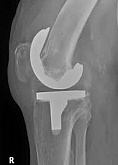

Еndoprosthesis of knee joint

In the late stages of arthrosis of the knee joint, accompanied by a pronounced restriction of the volume of movements, constant intense pain, deformity of the limb, the only way to recover is to replace the affected joint with an artificial joint - arthroplasty.

This method allows you to return the correct form of the limb, the full volume of movements in the joint, relieve the constant pain and crunch during movements and, as a result, significantly improve the patient's quality of life.

Below are presented X-ray photographs and photographs, illustrating the amount of motion in the affected joint before and after surgery.